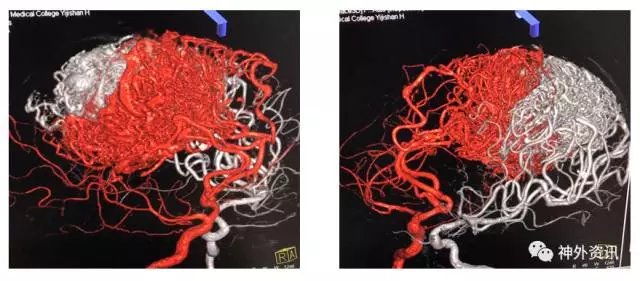

(3D重建:动脉瘤形态极不规则,远/近端血管迂曲严重伴狭窄)

(术后3D双容积重建)